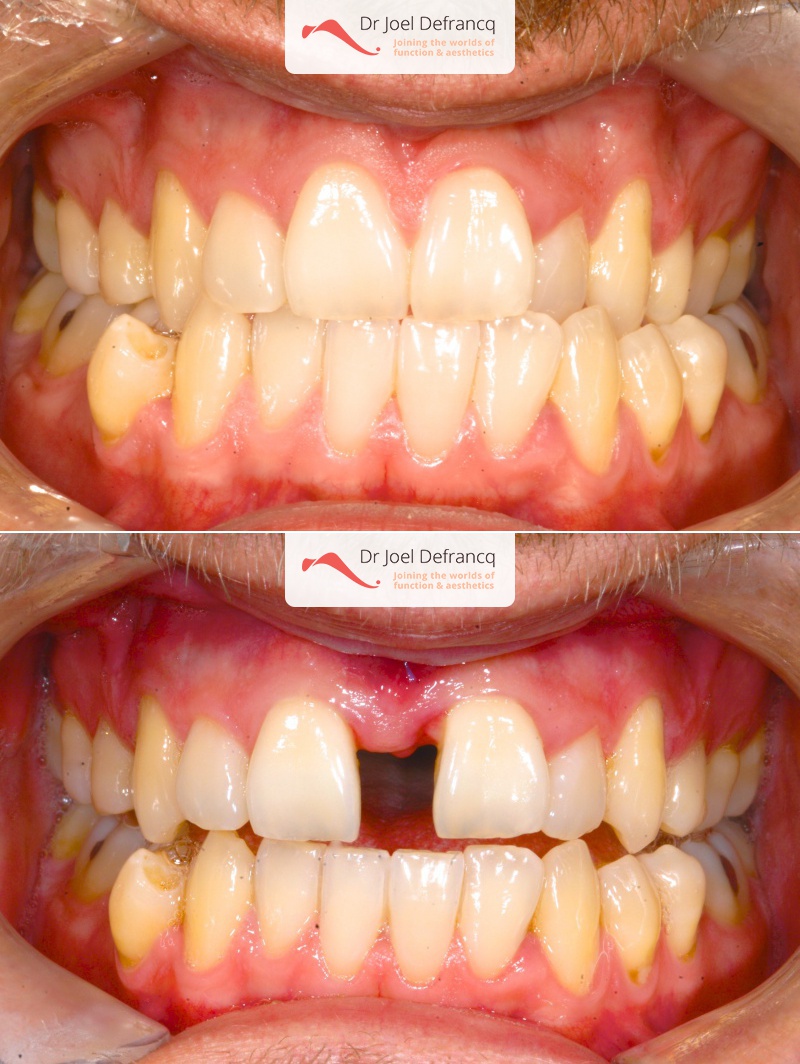

Natan: Kaakchirurgie voor en na. Te nauwe bovenkaak

Diagnose van het gezicht

- Te kleine bovenkaak

Dentale diagnose

- Klasse III

- Randbeet

Kaakchirurgie

- Verlenging bovenkaak (Le Fort I)

- Verbreden bovenkaak (Smile distractor)